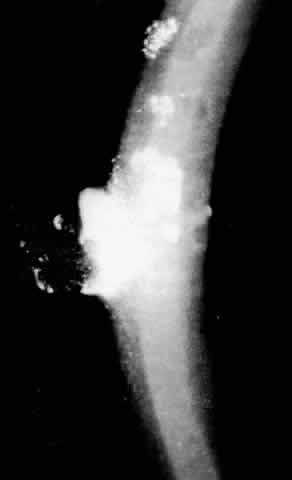

The most common findings are the maplike opacities (Figs. 1 AND 2), which can be detected by wide oblique illumination.8 The dot changes (Fig. 3) are seen by direct illumination, and fingerprint lines (Fig. 4) often need indirect illumination from the iris or retroillumination for detection. The distribution of the lesions can change over time.

Fig. 3. Epithelial basement dystrophy: grayish-white putty-like dot opacities.